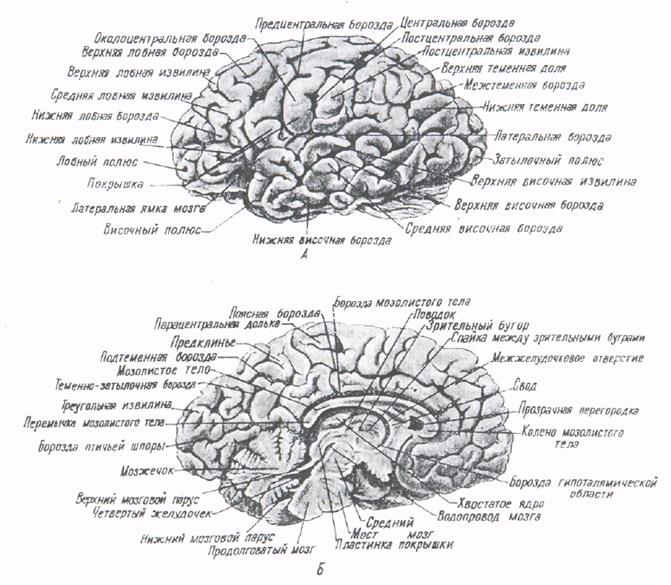

Анатомические снимки верхнелатеральной поверхности головного мозга